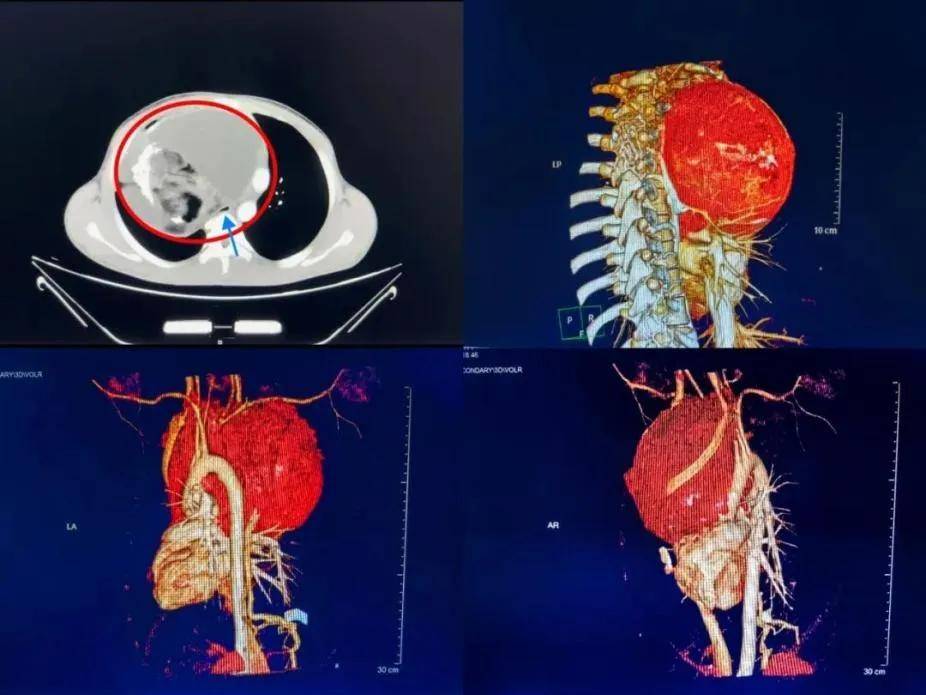

华西胸外科,骨科专家联合实施高难度手术,完整切除!